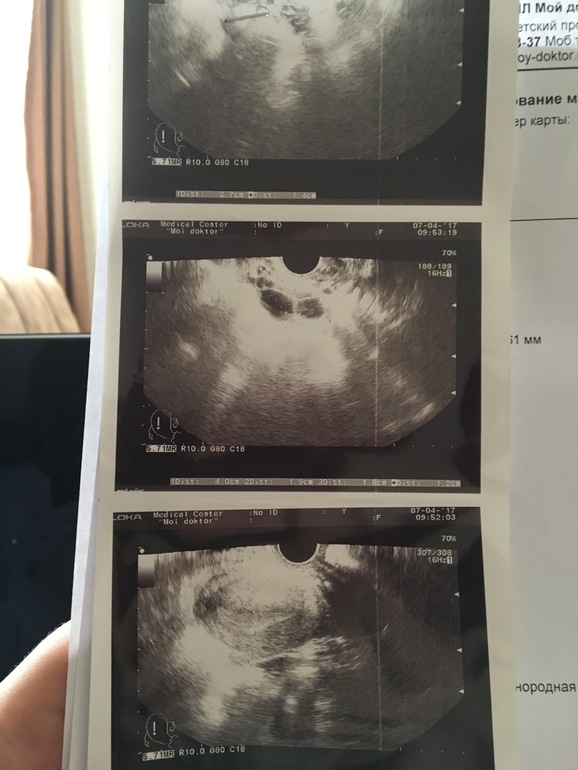

это Жт или фолликул

Овуляция( тесты на овуляцию)Я знаю я вас достала, но кроме вас мне бежать некуда , девочки кто понимает скажите Это ЖТ или фолликул ?

Жт, насколько я видела на своих узи, с неровными краями. А вот когда шарик, это фолликул

По моему взгляду больше на фолликулы похоже. Могу ошибаться. А что в заключении узи? И какой дц?

узи от 4 апреля обьем матки 76,44 см3 эндометрий 9,5 мм соответствует фазе секреции. правый яичник, структура однородное ЖТ.

узи от 7 апреля обьем матки 94,56см3 эндометрий 10мм правый яичник структура однородная с фолликулами от 16 до 12 мм. жидкость в позадиматочном пространстве не выявлена , заключение на море. исследования эхографические признаки секретной фазы мц, сегодня узи от 10 апреля, схоже по заключению от 7 апреля но на сегодня эндометрий 8мм. и так что мы имеем , 8 дней задержку тесты на Б то слабоположительные то пустые. Я запуталась , скажите что мне делать , и что все таки у меня , была овуляция или будет и из за чего задержка ?